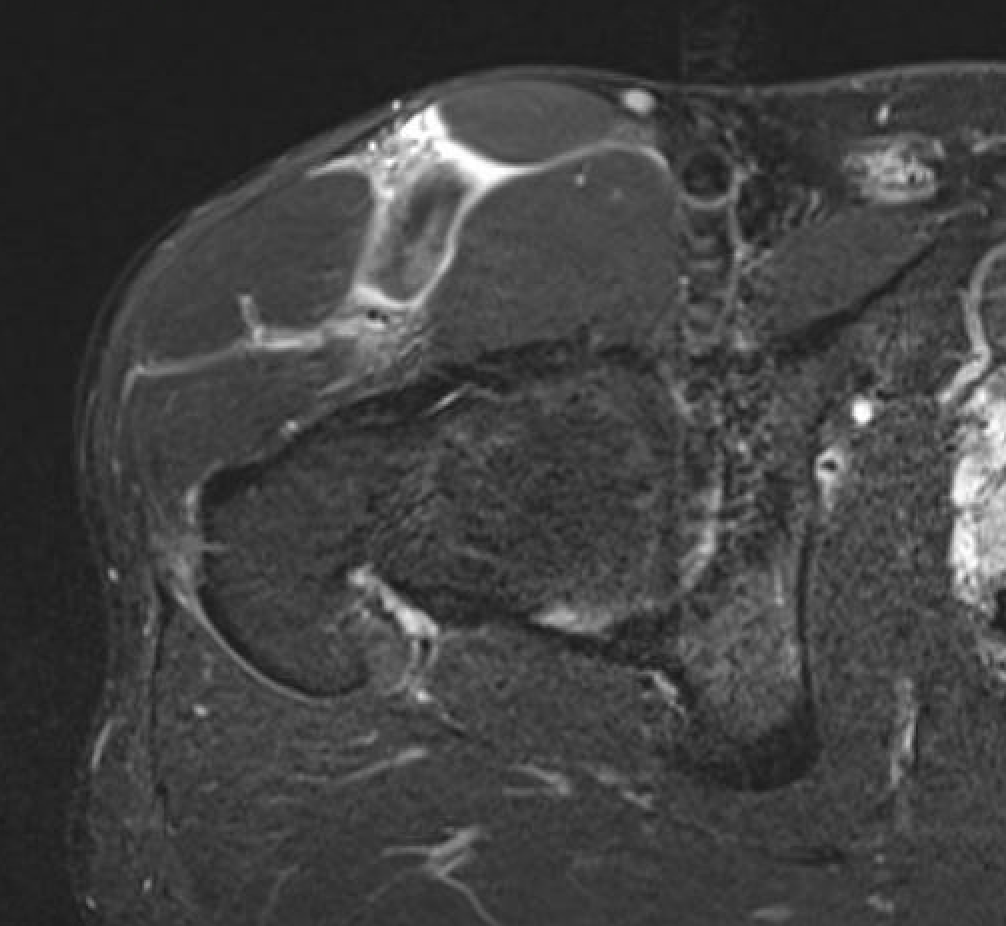

Grade 3C proximal central tendon rectus femoris